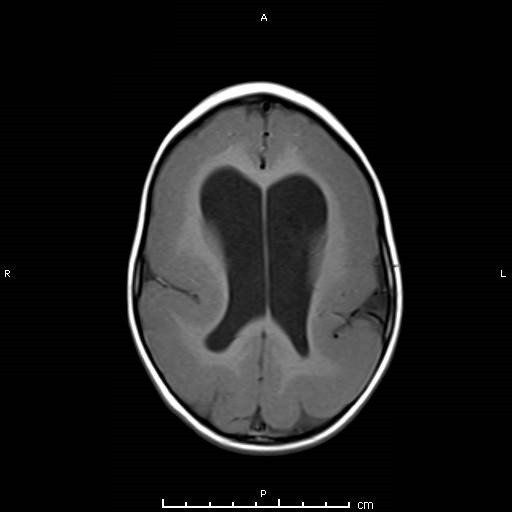

Características de Imagens

A lisencefalia inclui uma variedade de malformações cerebrais graves, incluindo agiria (giro ausente), paquigiria (giro amplo) e heterotopia de banda subcortical. Na lisencefalia (que significa literalmente cérebro liso), a superfície do cérebro parece lisa. Pode ocorrer isoladamente ou em associação com outras síndromes (síndrome de Miller-Dieker).

A lisencefalia é causada por um defeito na migração neuronal durante o desenvolvimento embrionário entre 12 e 24 semanas de gestação que resulta na ausência de desenvolvimento normal dos giros e sulcos cerebrais. Crianças com lisencefalia apresentam atrasos significativos no desenvolvimento e deficiência mental, mas variam de criança para criança, dependendo do grau de malformação cerebral.